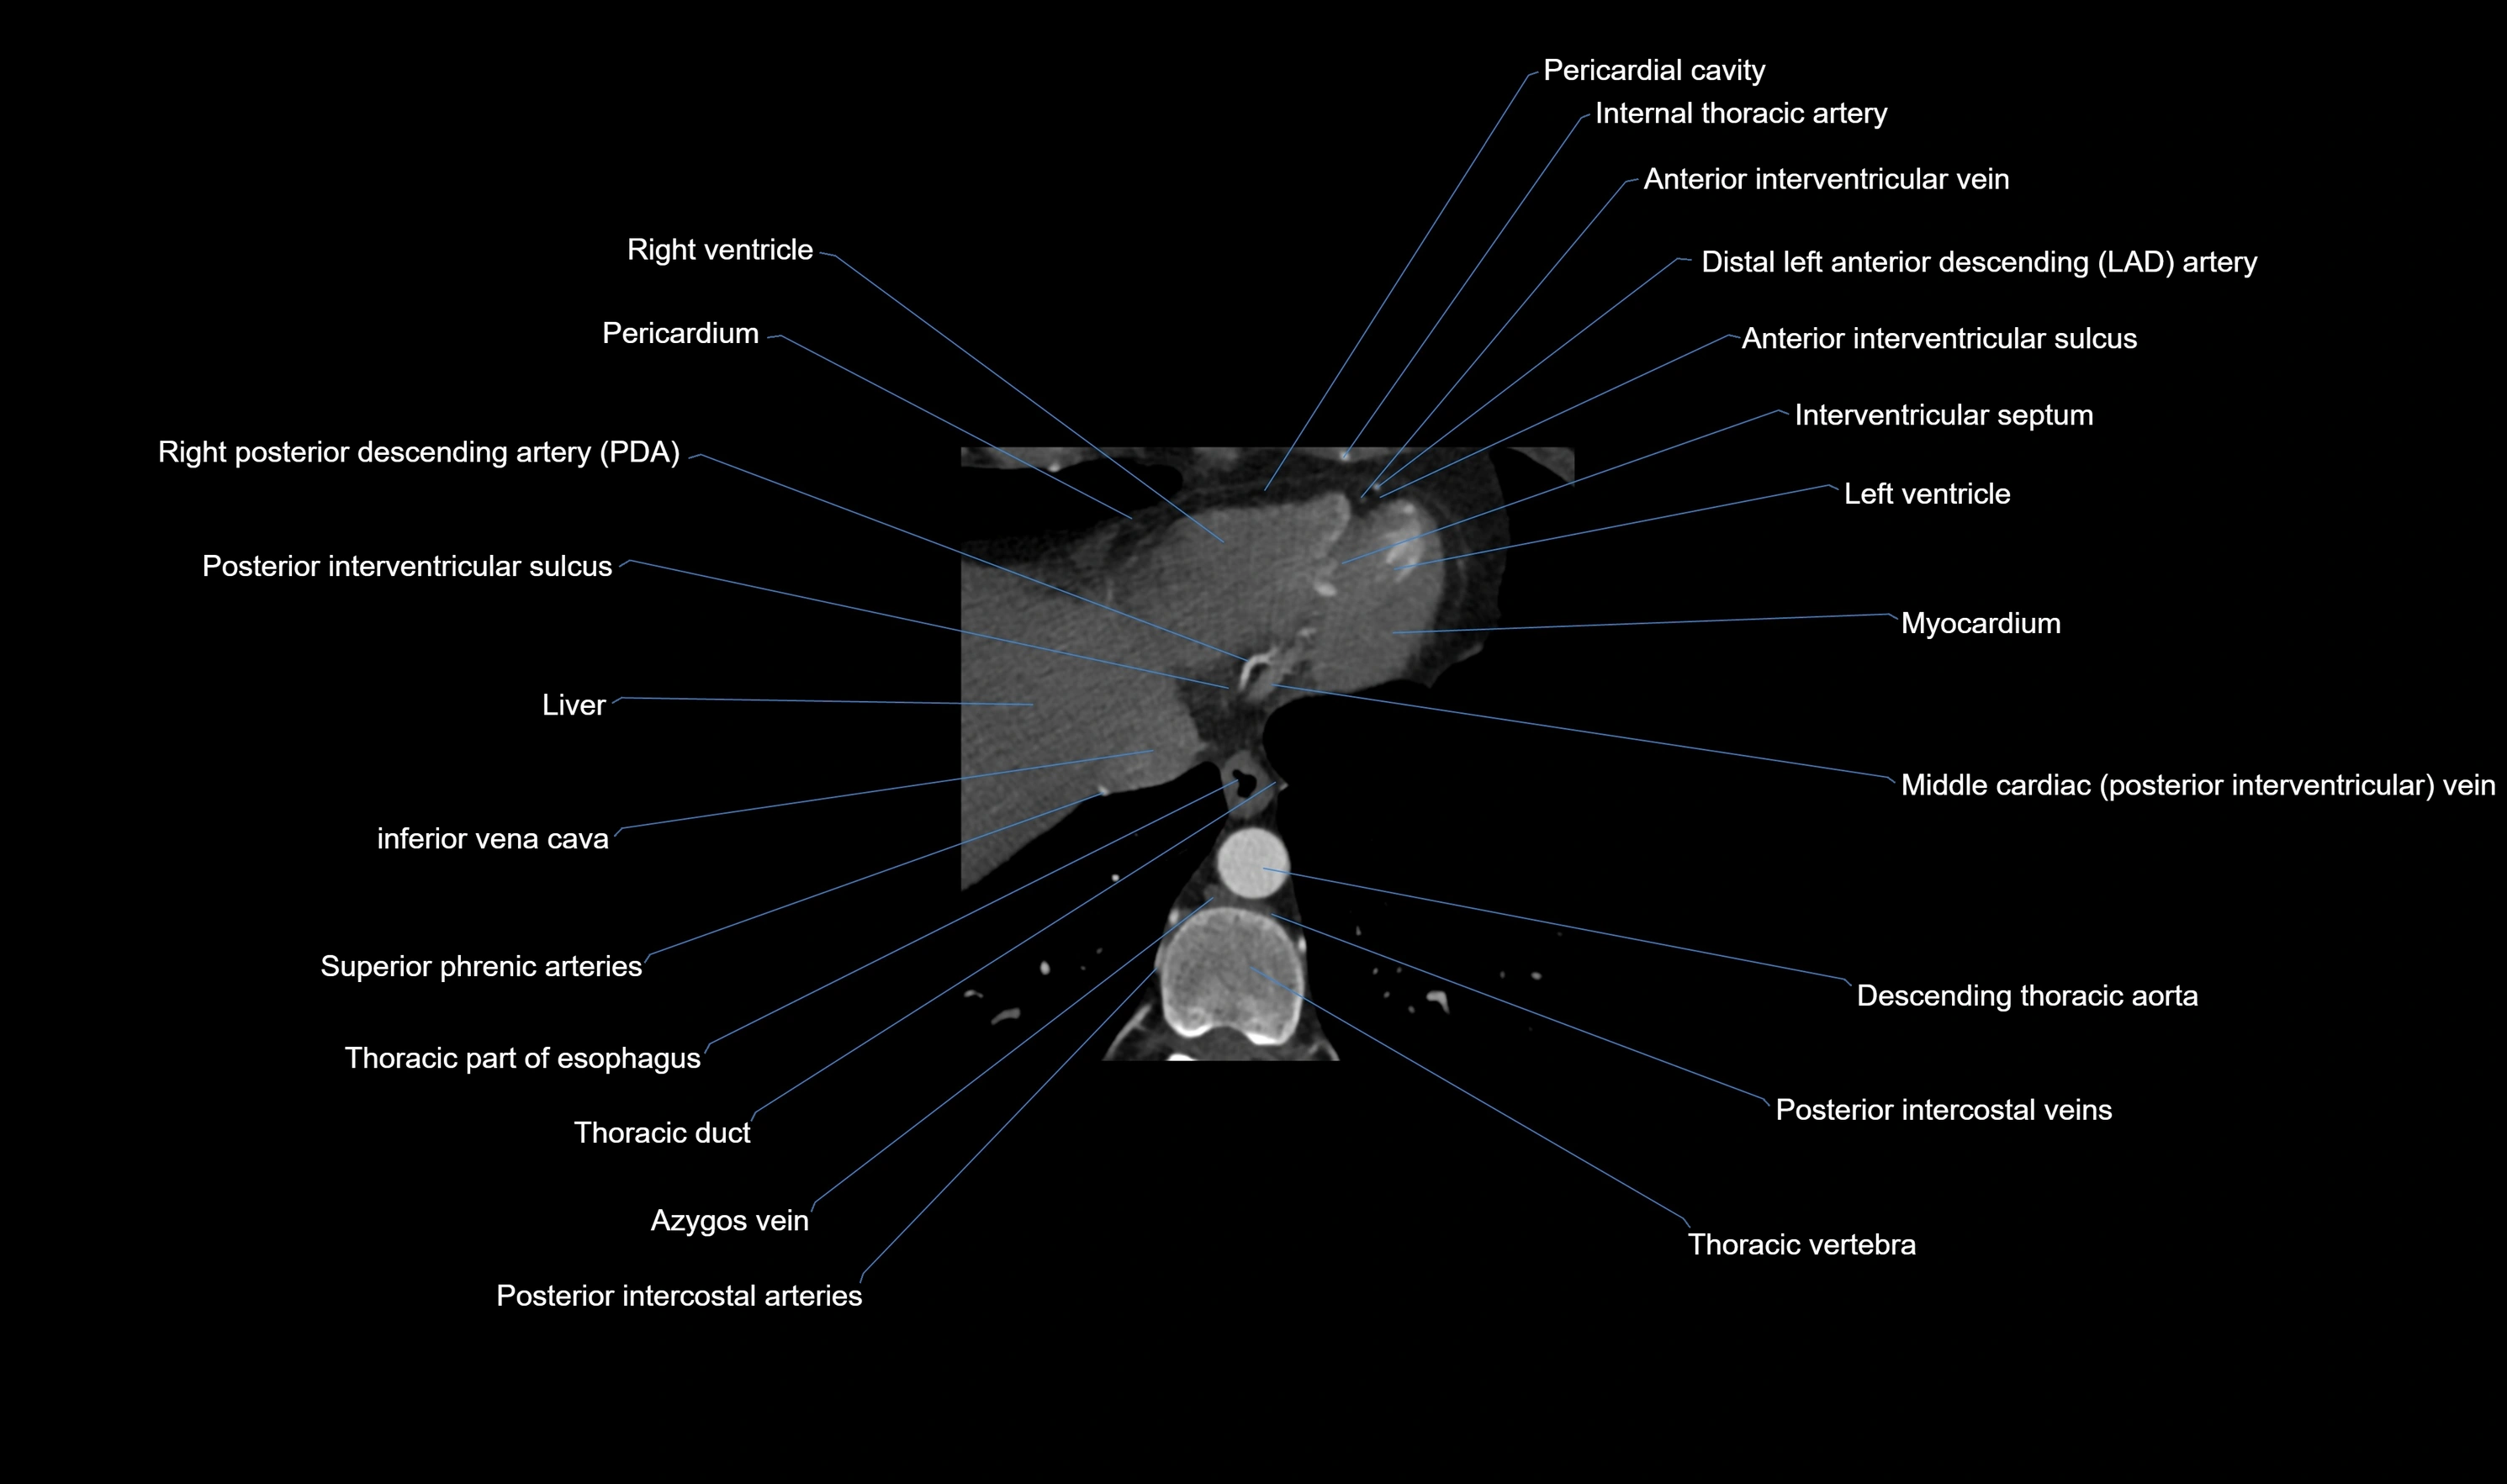

CT Appearance

CT Coronary Angiography (CCTA):

-

Best non-invasive modality for acute marginal artery visualization

Shows origin, course along the acute margin, and right ventricular branches

Detects stenosis, occlusion, calcified and non-calcified plaques, aneurysm, or anomalous course

Multiplanar reformats and 3D reconstructions help in pre-PCI and surgical planning

Critical for assessing right ventricular infarction risk in RCA disease

MRI image

CT images